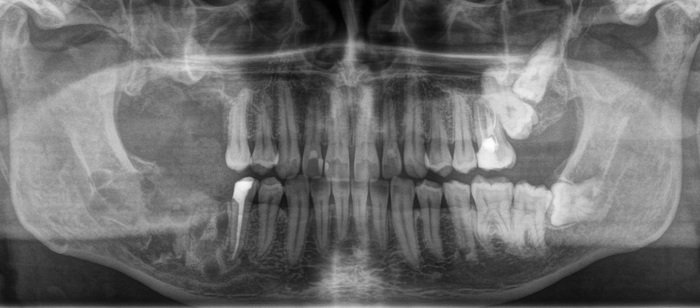

После изучения снимка и дополнительной консультации с терапевтом были приговорены практически все жевательные зубы, кроме левой нижней шестерки. (На снимке справа)

После того, как я предупредил о ВСЕХ возможных рисках и последствиях, плюс о шансе, что условий для имплантации на верхней челюсти в дальнейшем может и не представиться, пациент согласился. Я начал с удаления зубов на верхней челюсти справа. (на снимке слева)

Как вы думаете, сколько ушло у меня на удаление этих трех зубов?